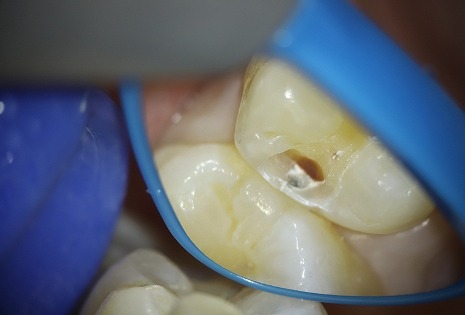

40代女性の虫歯治療

術前・術中

歯に亀裂が入って、そこから虫歯菌が侵入して短期間で深い虫歯になっていました。

古い詰め物が入っている歯や、食いしばりがある方によくできる虫歯です。